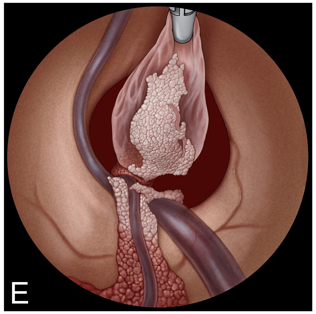

E:将囊肿移入侧脑室。

F:采用双手手术技术暴露囊肿蒂。通过左侧通道插入一把可弯曲的抓钳。主要手术器械通过 2.9 毫米的直工作通道引入。

G:用双极电凝器采用双手手术技术凝固囊肿蒂。

H:用剪刀采用双手手术技术切断囊肿蒂。

I:囊肿切除后检查室间孔。